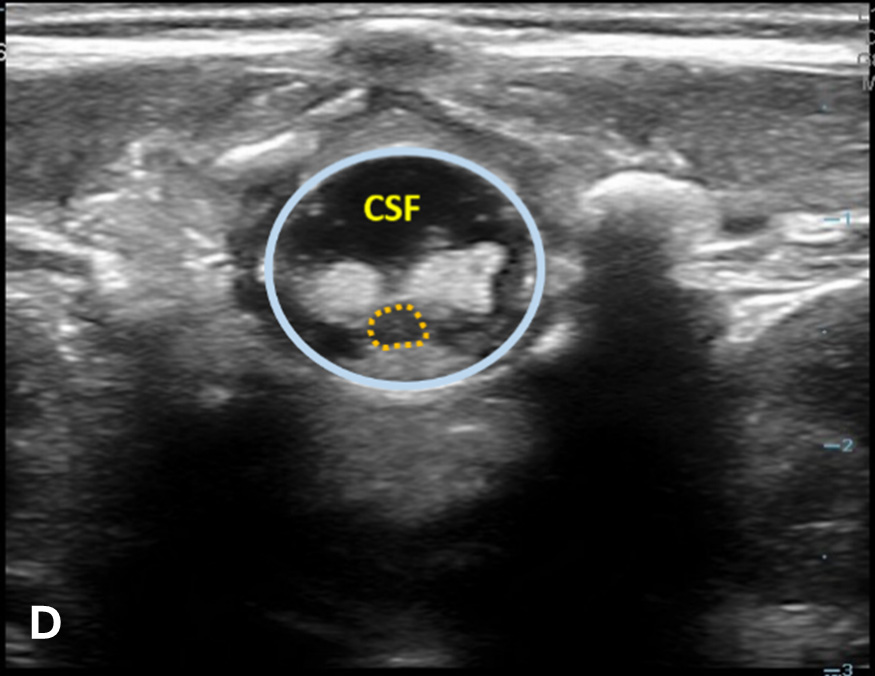

The transverse view should also be obtained to verify landmarks and identify any overlying vessels or hematomas (from prior attempts) to avoid. The transducer is rotated to the transverse position on the lower back and moved caudally over the spinous processes to locate the CM, which is a hypoechoic structure positioned in the center of the spinal canal. At higher levels of the CM, the ventral roots and dorsal roots can be identified, which are surrounded by the anechoic CSF. Next, gradually move the transducer caudally and observe the CM decreasing in size while being encircled by the hyperechoic fibers of the CE. (Figure 2) Once this sonographic landmark is identified, locate the center of the transducer and mark the corresponding area on the skin, aligning it with the center of the spinal cord. Subsequently, draw lines from both markers in both planes and utilize the point of intersection as a guide for inserting the LP needle. To enhance visualization of the spinal cord’s vascular supply, and avoid a space with any overlying vessels that may cause a traumatic tap, it is advisable to apply color Doppler in both the sagittal/longitudinal and transverse views.9 (Figure 3)

Figure 2 - Corresponding US image showing spinal canal structures in transverse view:

Figure 2 - Corresponding US image showing spinal canal structures in transverse view. 2A-B: The caudal portion of the transverse view shows DR (dorsal roots), VR (ventral roots), CSF (cerebrospinal fluid), and CM (conus medullaris). 2C-D: The probe is moved caudally demonstrating the tapered CM (orange dotted circle), CE (cauda equina, hyperechoic structure surrounding the CM) and a pocket of CSF. 2E-F: Demonstrate the disappearance of the CM, and the pocket of CSF becoming larger as the probe was moved caudally. The blue circle is the entire dural sac encircling the spinal canal.